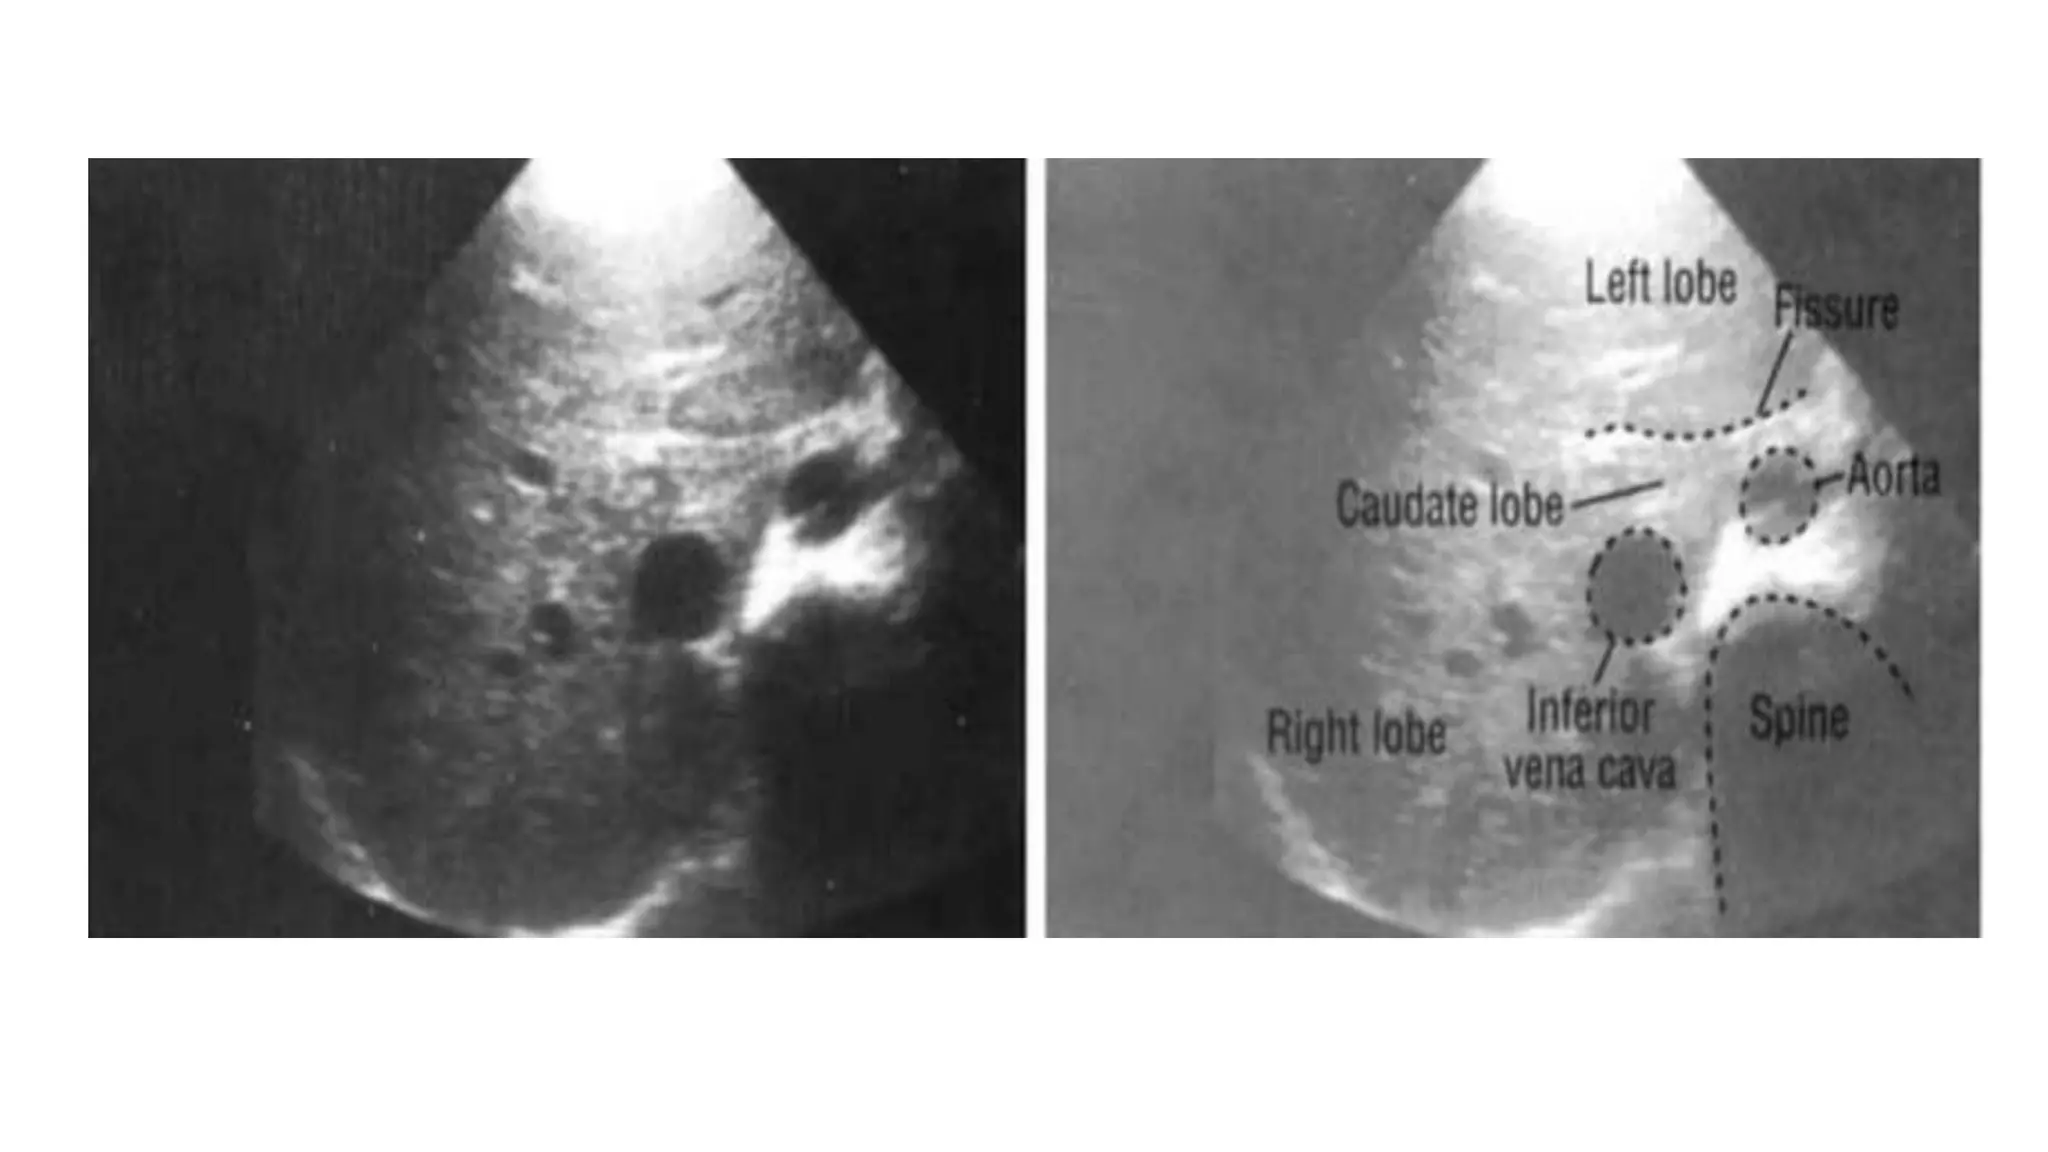

Structure of the Human Body Amy Kule, MD (akule@lumc.edu) Click here to enter a date. Student Version . Abdominal Aorta and Inferior Vena Cava Ultrasound . Describe normal ultrasound anatomy of the abdominal great vessels, including the aorta, inferior vena cava, its branches, as well as its relationship with surrounding structures

The document provides an overview of abdominal ultrasound anatomy and techniques for examining various abdominal organs. It describes the liver anatomy, including Couinaud's segments. It outlines scanning techniques for the liver, gallbladder, pancreas, spleen, aorta, kidneys, bladder, prostate, uterus, ovaries, appendix, and gastrointestinal